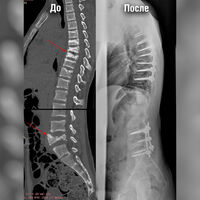

Мальчику провели комплекс обследований, в том числе КТ и МРТ позвоночника, по результатам которых врачи обнаружили компрессионные переломы позвонков в грудном и поясничном отделе. Для проведения экстренной операции по фиксации переломов врачам необходимо было стабилизировать состояние пациента.

Стандартным подходом к лечению компрессионных переломов позвоночника является транспедикулярная фиксация при помощи металлоконструкции — сложная высокотехнологичная операция.

«Мы получили доступ к области переломов, установили в тела позвонков специальные винты, после чего соединили их стержнями. Всего было установлено две металлоконструкции — протяженностью в семь позвонков грудного отдела и в три позвонка поясничного. Затем мы уложили их костным аутотрансплантатом, чтобы обеспечить максимальную стабильность в дальнейшем», — рассказал о ходе оперативного вмешательства Андрей Пантелеев.